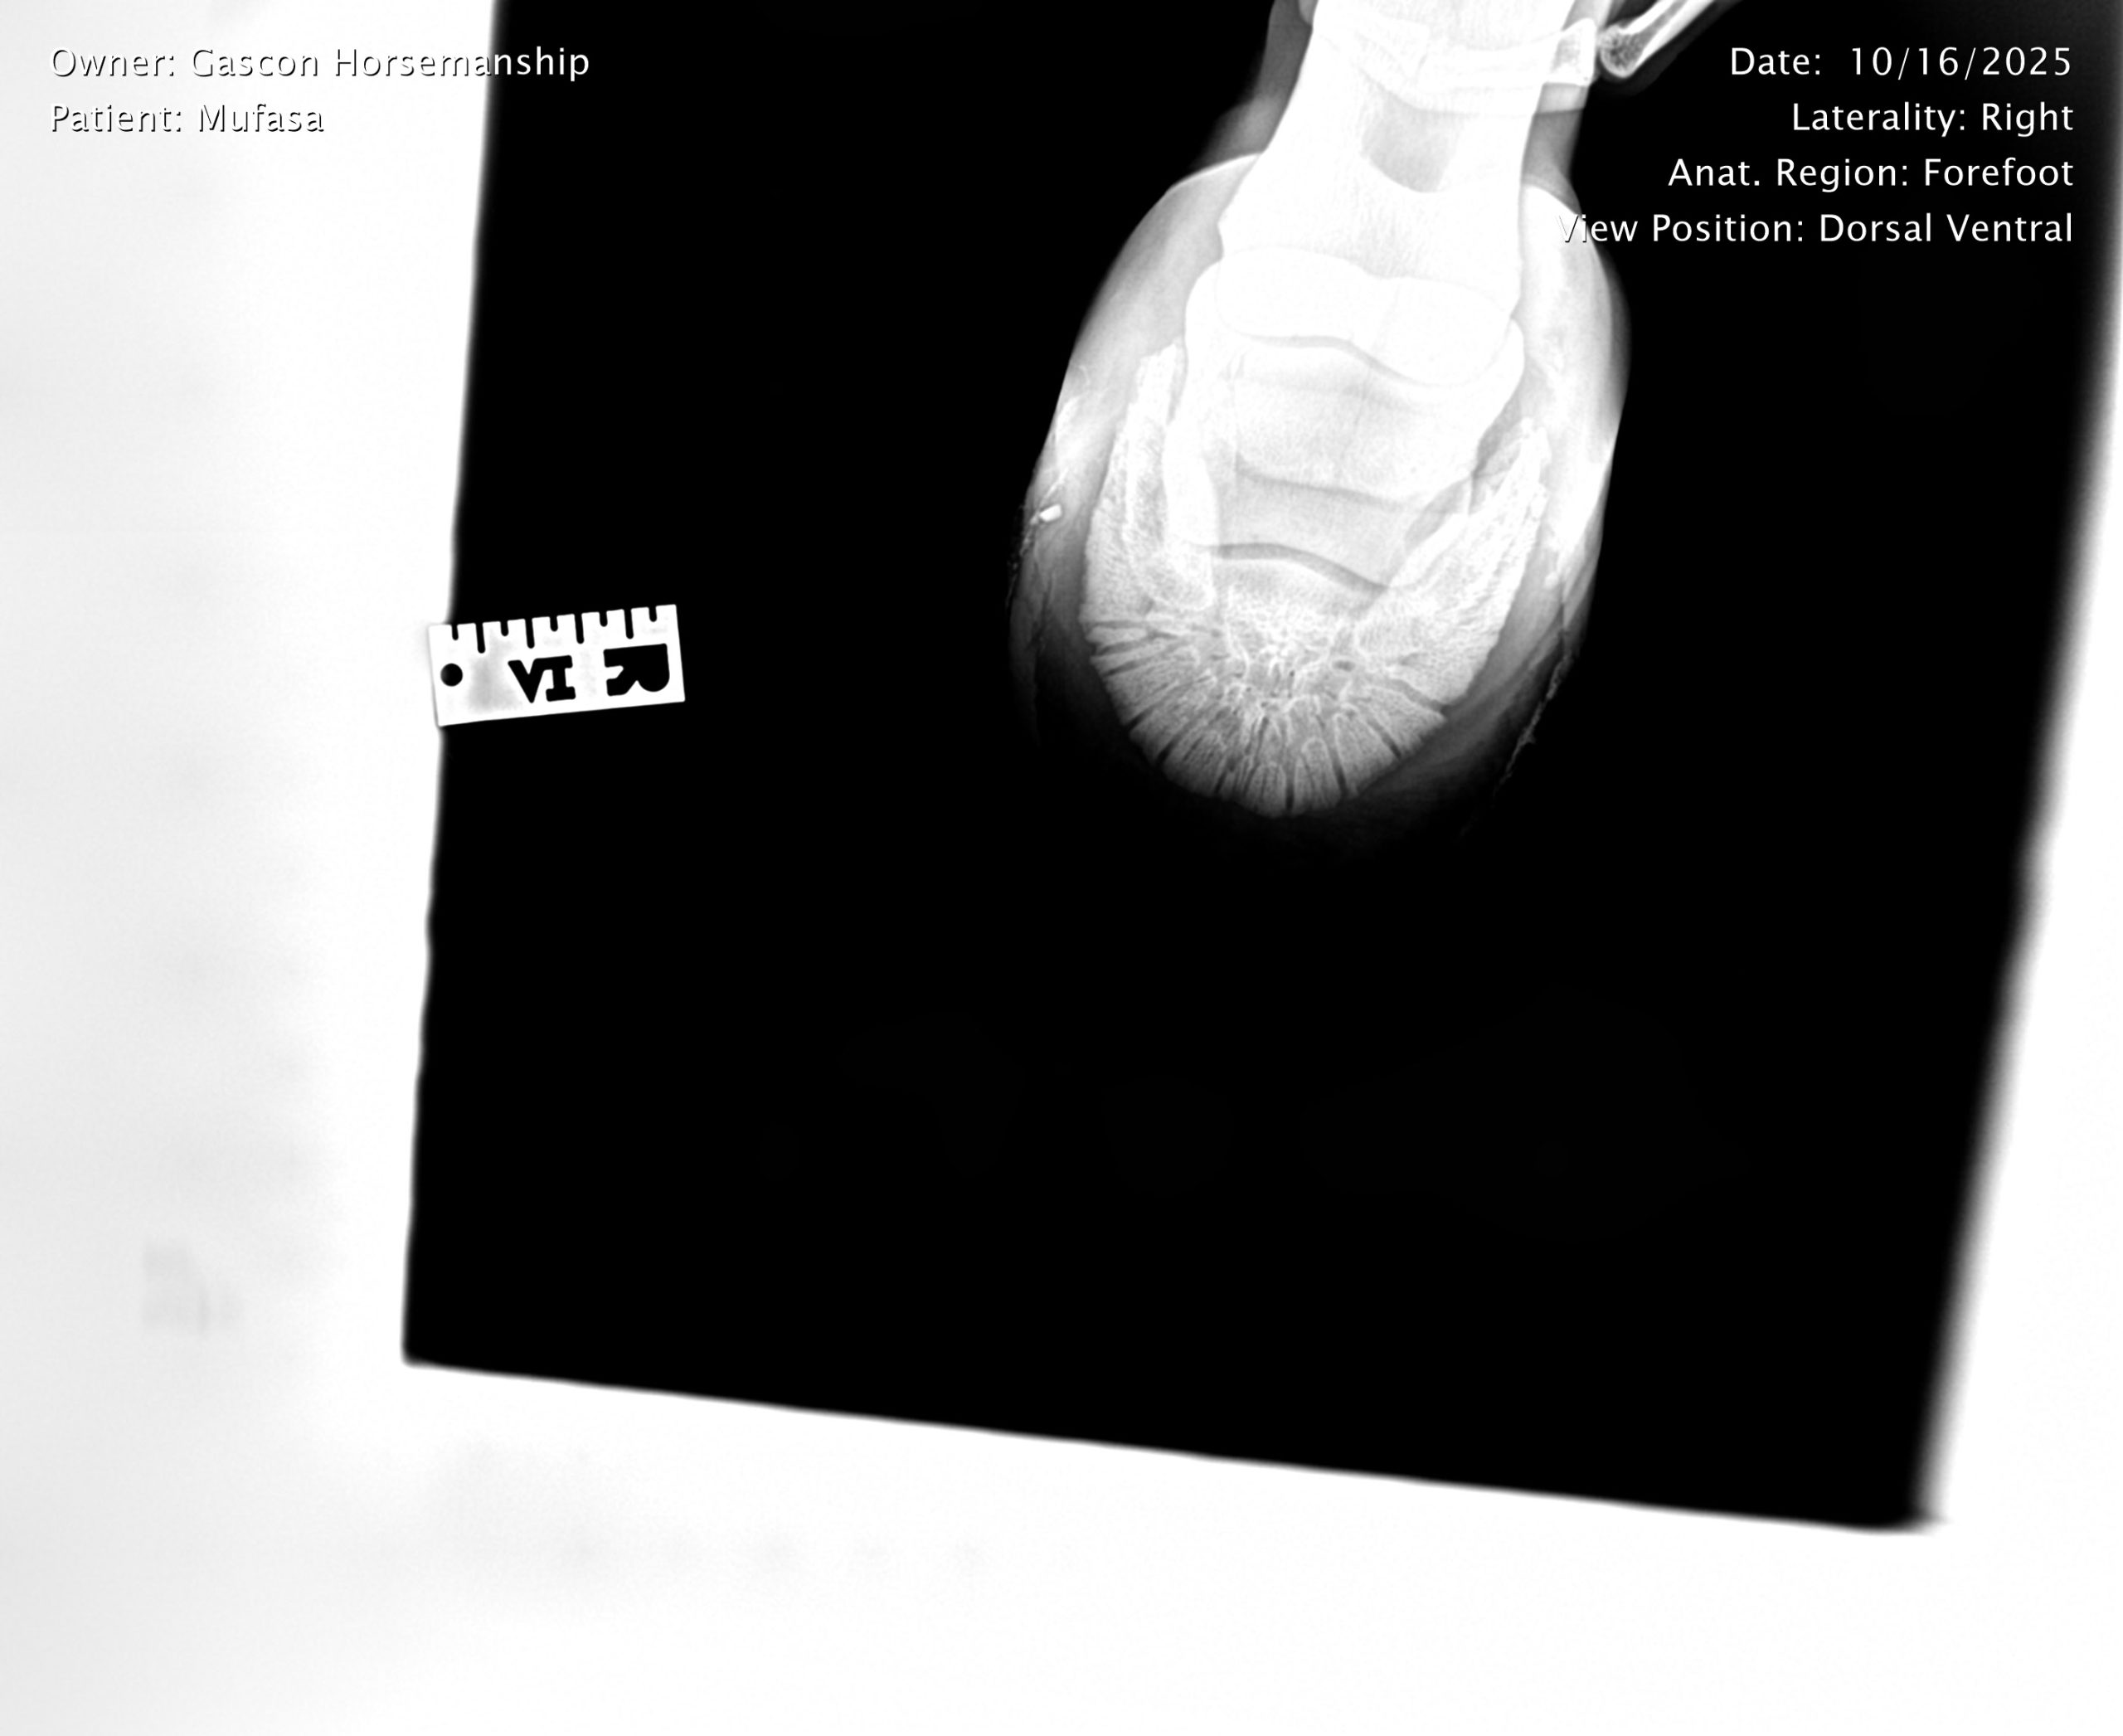

He already has a full pre-purchase exam on file, complete with 25 X-rays included in his album.